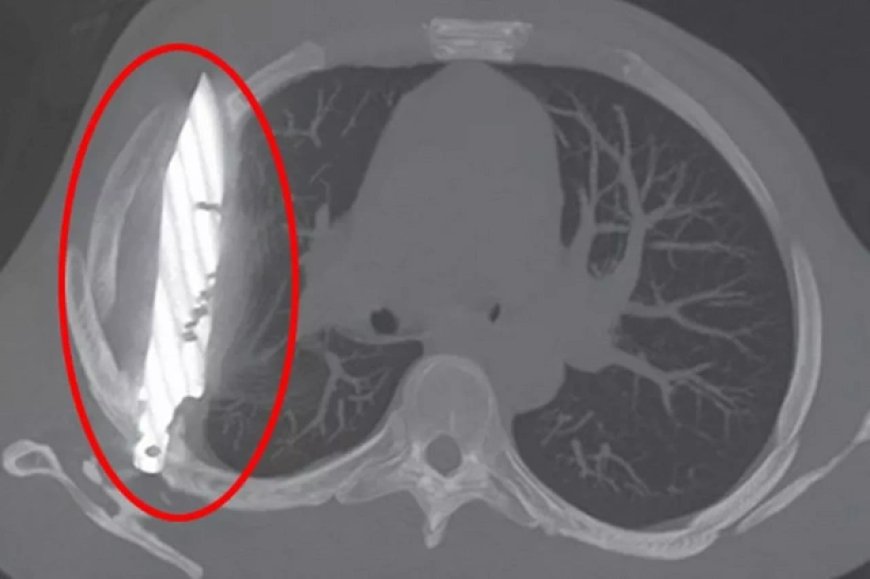

Müəyyən olub ki, xəstə on il əvvəl bir neçə bıçaq xəsarəti alıb. Bir müddət sonra onun yaraları sağalıb və irin görünənə qədər o, sinəsindəki bıçaqdan xəbərsiz yaşayıb. Rentgen müayinəsi göstərib ki, onun sinəsində böyük bıçaq tiyəsi ilişib qalıb. Bıçağın tiyəsi onun sağ kürək nahiyəsindən daxil olub, lakin həyati orqanlarına toxunmayıb.